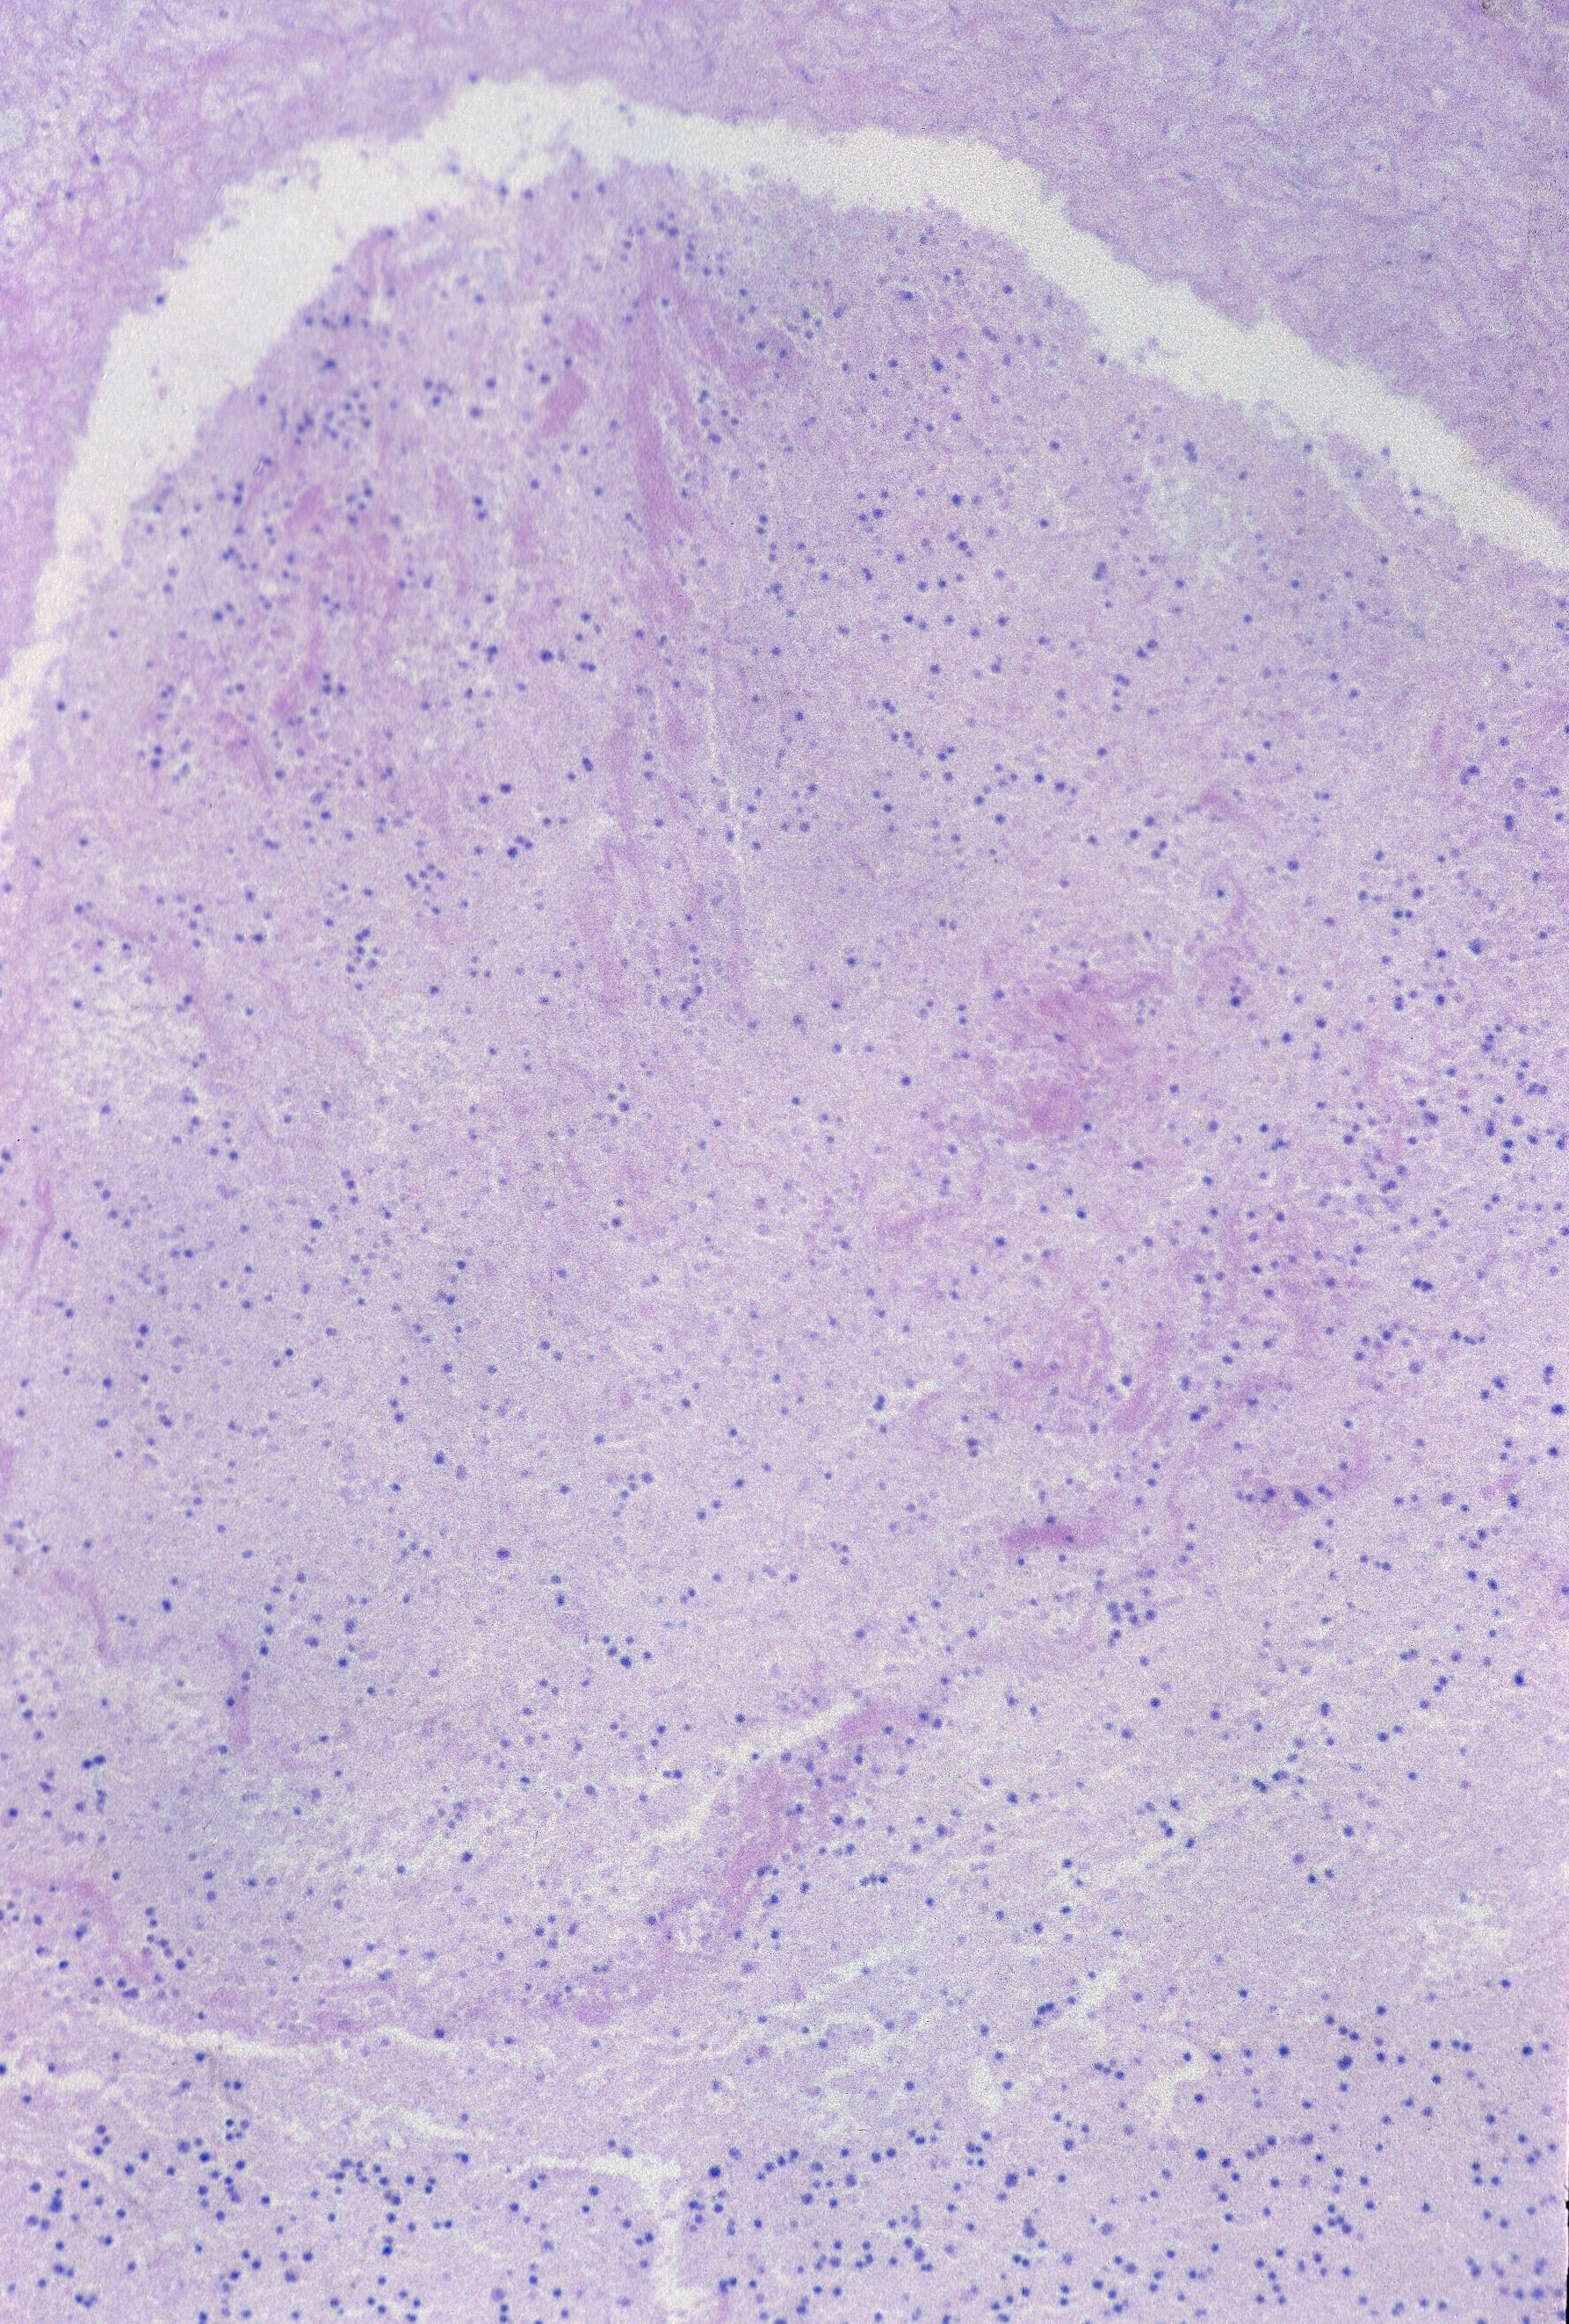

The loss of more than 1% of hepatocyte nuclear basophilia occurs in the window after 24 hours of postmortem retention (Fig 18)10.

Complete loss of basophilia occurs after 96 hours. A peculiar artifact in early gestation fetuses with prolonged retention is the expulsion of brain tissue inot the body presumably during delivery through a narrowly dilated cervix. This often extrudes through the spinal foramina, but also can be driven into the venous drainage of the heart into the hepatic circulation. This artifact has been mistaken for tumor as the small blue cells retain nuclear basophilia longer than other tissues, but the diagnosis can be made by the collapse of and the loss of brain issue within, the skull (Fig 19).